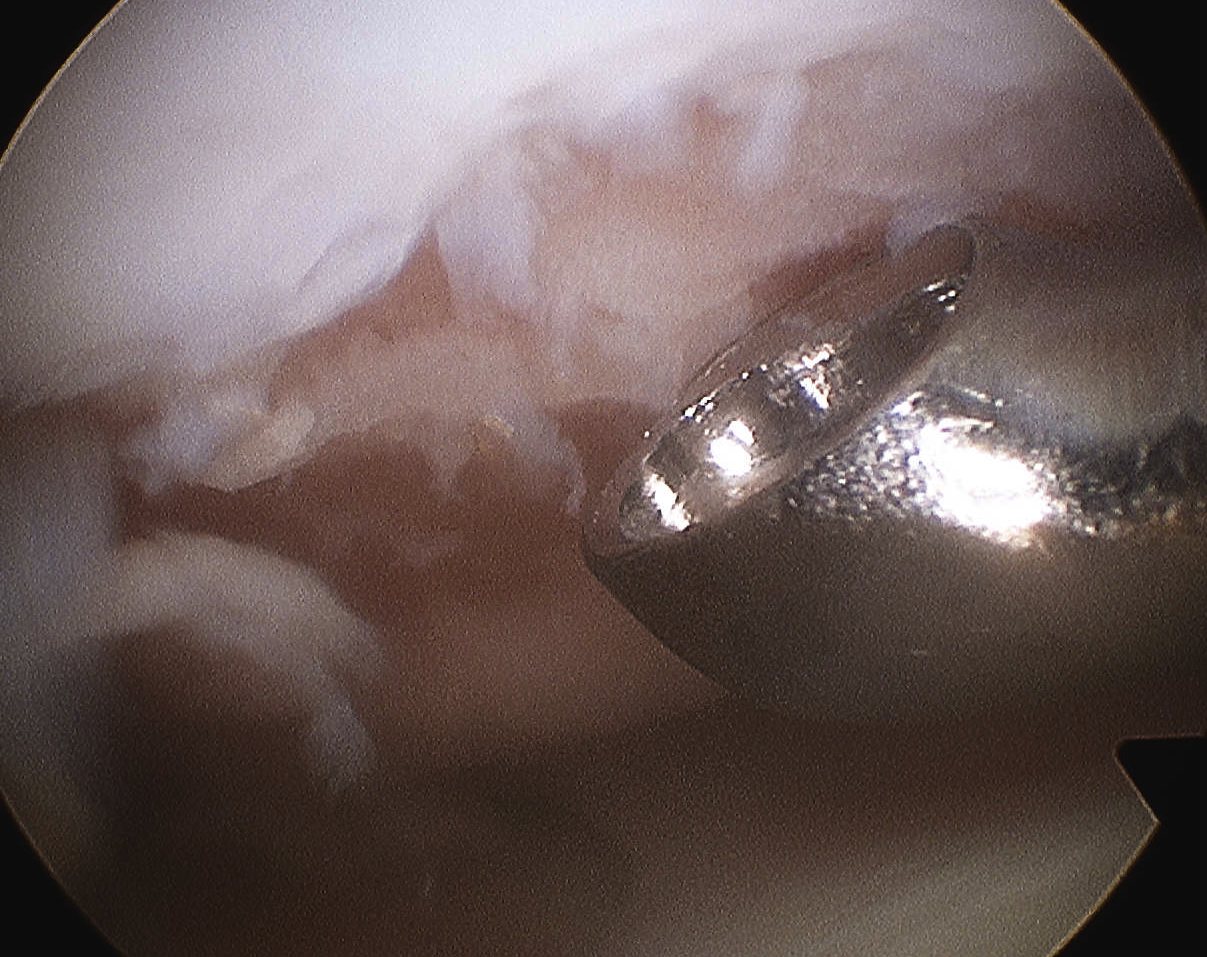

Arthroscopic microfracture awl / 1.6 mm drill

- typically 3-4 mm apart

- depth until see fat globules

Post arthroscopic drilling with K wire